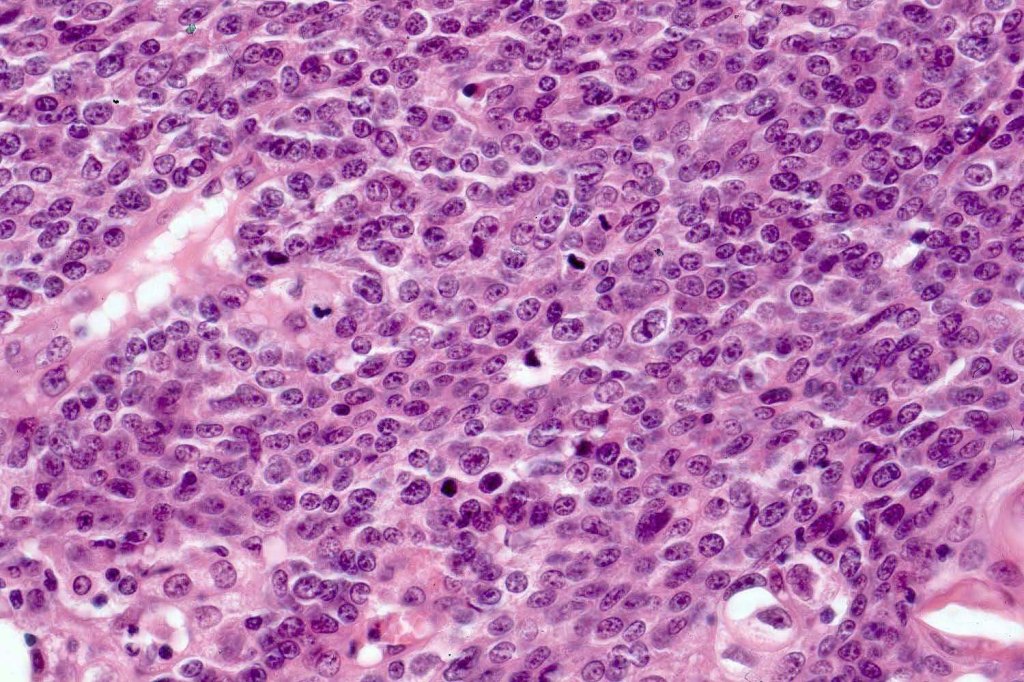

•Tumors are composed of an admixture of darkly staining basaloid cells with hyperchromatic or vesicular nuclei and more obvious sebaceous cells with eosinophilic, bubbly, multivacuolated cytoplasm frequently indenting the nucleus (scalloped)

•Often mitoses are numerous and abnormal forms evident

•May be graded into well, moderate & poorly differentiated categories. I am not sure that this has any great value

Sebaceous carcinoma from a patient with Muir-Torre syndrome kindly shared by Dr. Antonina Kalmykova.